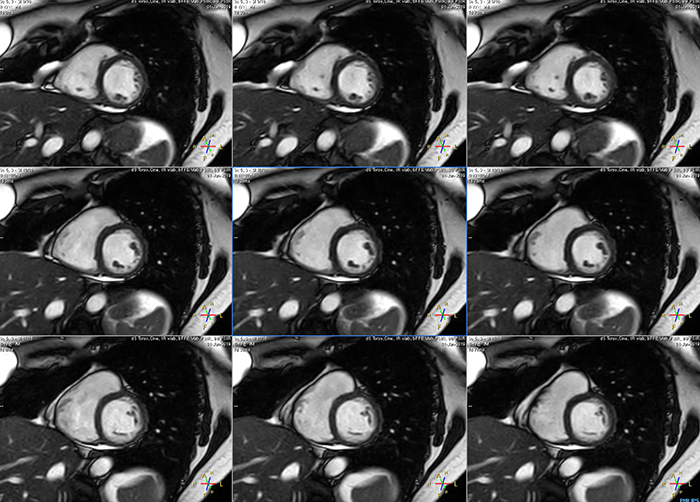

These are some images of a cardiac cine scan with a short breath-hold time. A high temporal resolution provides a smooth cine, which helps in assessing heart function. Ingenia Ambition.

Avila says that Compressed SENSE allows them to reduce breathhold time to 3 to 4 seconds in cardiac cine scans. “At the same time, we can now – based on cardiac frequency – obtain as many as 30 to 40 cardiac phases without sacrificing resolution, while before Ingenia Ambition, we were acquiring only 20 phases.

“This ability to use Compressed SENSE for obtaining higher temporal resolution translates to a much smoother cine. This allows me to better assess heart function,” Dr. Peña says.